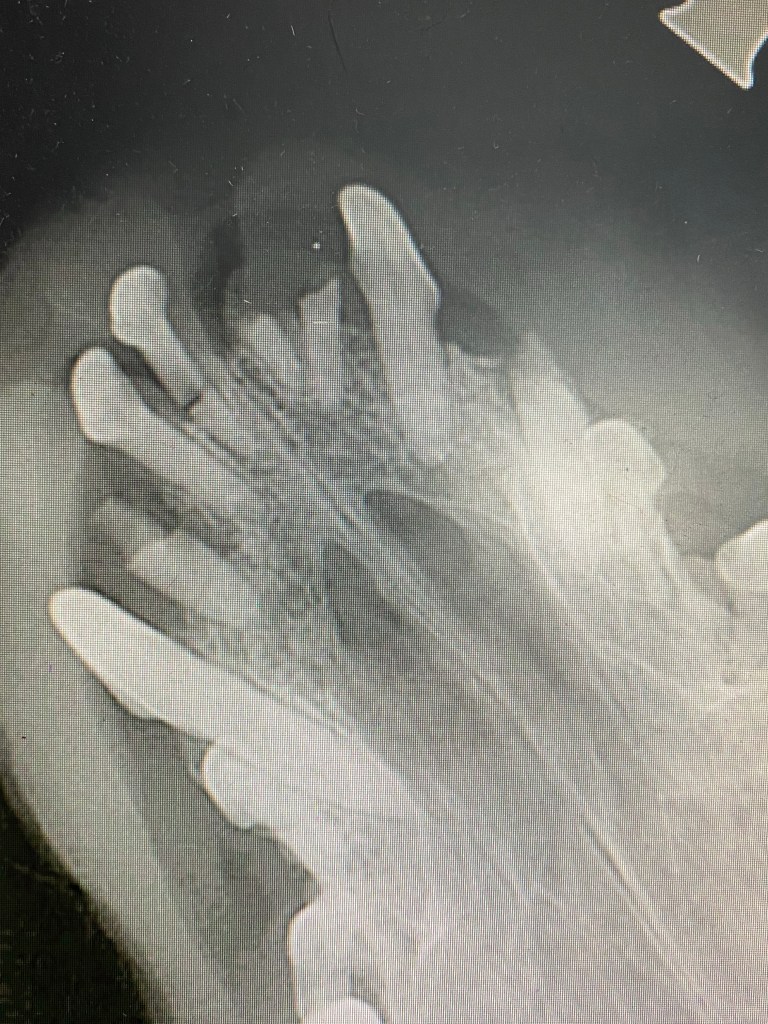

My work in Aberdeen was a nice mix of consultations and of operations which included some dental work.

I was grateful that the clinic featured a state of the art dental radiography system for this and that the team went to great length to provide high quality images.

The importance of this was highlighted when a small dog with some missing teeth and a completely unrelated problem turned out to have a number of retained (and probably very painful) roots and fractured teeth, even if this subsequently impacted severely on the duration of my lunch break that day….